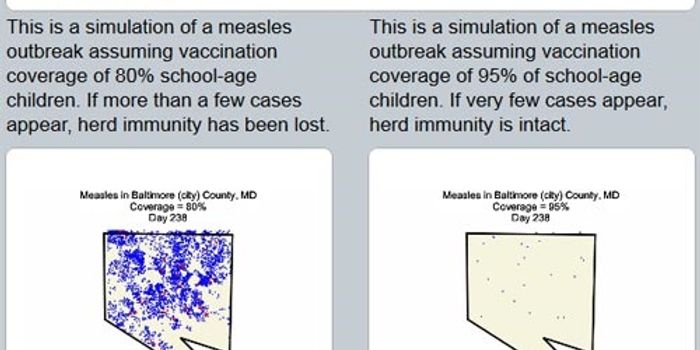

AUG 29, 2017InfographicsOver the years, vaccines have prevented countless cases of disease and saved millions of lives. Currently, there are ove ...